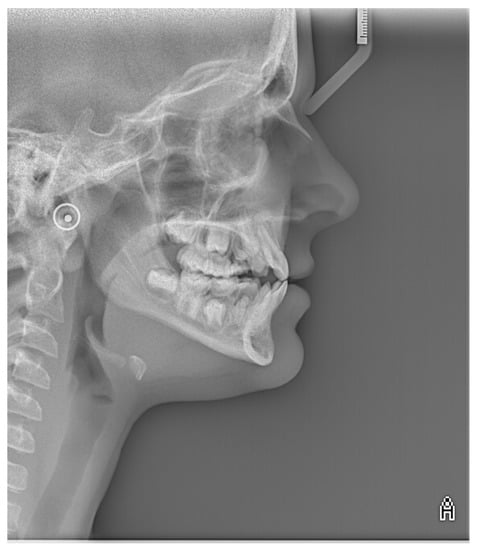

2.4. Radiological Examination